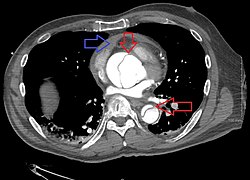

Aortic dissection

CT with contrast demonstrating aneurysmal dilation and a dissection of the ascending aorta (type A Stanford)

Chest CT with descending (type B Stanford) aortic dissection (red circle)

Computed tomography angiography is a fast, noninvasive test that gives an accurate three-dimensional view of the aorta. These images are produced by taking rapid, thin-cut slices of the chest and abdomen, and combining them in the computer to create cross-sectional slices. To delineate the aorta to the accuracy necessary to make the proper diagnosis, an iodinated contrast material is injected into a peripheral vein. Contrast is injected and the scan performed using a bolus tracking method. This type of scan is timed to an injection to capture the contrast as it enters the aorta. The scan then follows the contrast as it flows through the vessel. It has a sensitivity of 96 to 100% and a specificity of 96 to 100%. Disadvantages include the need for iodinated contrast material and the inability to diagnose the site of the intimal tear.